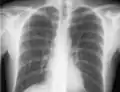

If a pneumothorax is suspected, an upright chest x-ray should be obtained. An upright chest x-ray is preferred because free air will migrate to the apex of the lung, where it is easily visualized. Of course, this is not always possible, particularly in critically ill patients in the intensive care unit. Radiographs obtained in the supine position fail to detect 25–50% of pneumothoraces.[6] Instead, bedside ultrasound is a superior method of detection in those too ill to obtain upright imaging.[3]

The line is then inserted using the Seldinger technique: a blunt guidewire is passed through the needle, then the needle is removed. A dilating device may be passed over the guidewire to expand the tract. Finally, the central line itself is then passed over the guidewire, which is then removed. All the lumens of the line are aspirated (to ensure that they are all positioned inside the vein) and flushed with either saline or heparin.[1] A chest X-ray may be performed afterwards to confirm that the line is positioned inside the superior vena cava and no pneumothorax was caused inadvertently. On anteroposterior X-rays, a catheter tip between 55 and 29 mm below the level of the carina is regarded as acceptable placement.[37] Electromagnetic tracking can be used to verify tip placement and provide guidance during insertion, obviating the need for the X-ray afterwards.

Chest x-ray with catheter in the right subclavian vein

The outline of superior vena cava on a chest X-ray is labeled at left.